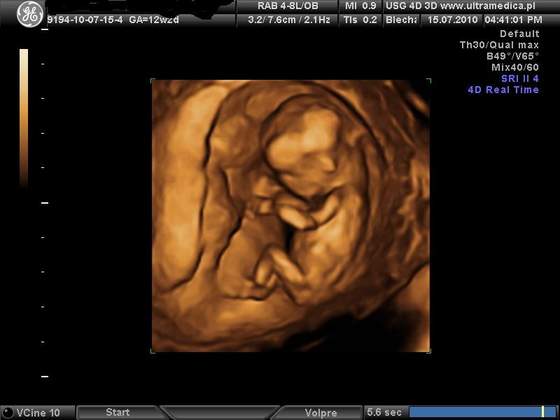

A ja dzisiaj byłam na usg. Okazało sie, ze maluszek jest o tydzien starszy niz na suwaczku, 13t5d, ma 7,7 cm wzrostu

Wrazenie naprawde niesamowite. Na poczatku maluszek spal, pozniej lekarz go budzil mocniej naciskajac brzuch. Zaczal machac raczkami, robic fikołki. Pozniej sie juz uspokoil, zaczal ssac paluszka i dal sie zmierzyc lekarzowi

Takze jestem dumna z mojego dzidziusia. Wszystko jest w porzadku wrecz ksiazkowo. Dostalismy kilka zdjec i płyte CD. Oczywiscie byl ze mna narzeczony. A co najlepsze znamy płeć

a oto ON: